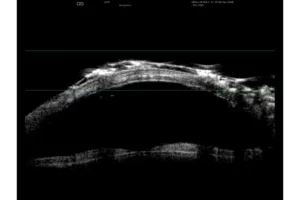

- Verhoogde scherptediepte waardoor het gehele oog zichtbaar is.

- Hoge resolutie die het mogelijk maakt om van het voorste gedeelte van het glasvocht tot aan de wand te zien.

- Nieuwe UBM technologie die verschillende beeldmodi mogelijk maakt.